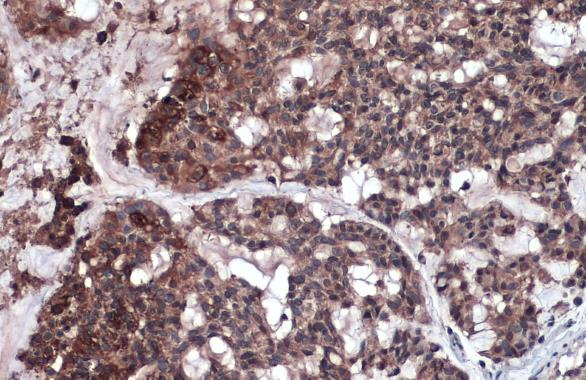

RIP3 antibody detects RIP3 protein at cytoplasm and nucleus by immunohistochemical analysis.

Sample: Paraffin-embedded human lung cancer.

RIP3 stained by RIP3 antibody (GTX131188) diluted at 1:500.

Antigen Retrieval: Citrate buffer, pH 6.0, 15 min

RIP3 antibody detects RIP3 protein at cytoplasm and nucleus by immunohistochemical analysis.

Sample: Paraffin-embedded human lung cancer.

RIP3 stained by RIP3 antibody (GTX131188) diluted at 1:500.

Antigen Retrieval: Citrate buffer, pH 6.0, 15 min